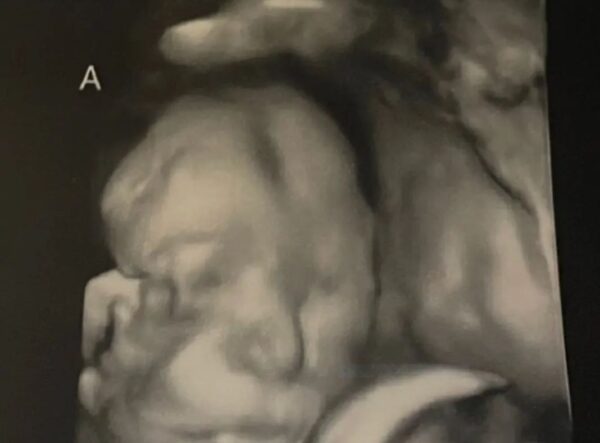

C’est à ce moment-là qu’ils ont fait l’échographie et qu’ils m’ont dit : « Oui, vous allez avoir des jumelles, mais elles sont très spéciales parce que ce sont des sœurs siamoises et qu’elles partagent un seul cœur », a confié Mme LeBlanc à Epoch Times. « J’ai failli perdre la tête. »

« Elles partageaient un seul cordon ombilical », a dit Nicole. « Elles avaient chacune leur petit derrière, leurs deux jambes et leurs deux bras. Elles partageaient un foie, un diaphragme et un intestin. »

Ses bébés étaient « vraiment minuscules » et Nicole ne pouvait pas encore les sentir bouger, mais elle avait vu les jumelles bouger leurs mains lors de l’échographie. Elle était ferme : elle ne voulait pas tuer ses bébés. »